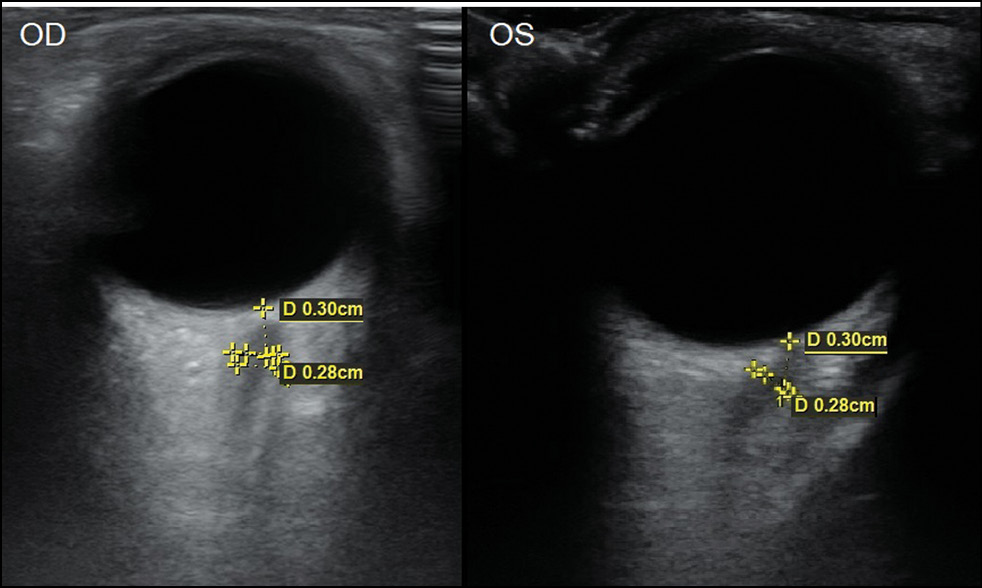

У 32 детей (64 глаза) с гипоплазией зрительного нерва наблюдалось значительное уменьшение показателя ТОЗН по сравнению с контролем во всех возрастных группах (р <0,05) (табл. 1, рис 3, 4).

Рис. 3. Эхограмма при атрофии зрительного нерва обоих глаз у девочки в возрасте 2 года. Биометрические показатели ретробульбарного отдела зрительного нерва правого (OD) и левого (OS) глаза.

Fig. 3. Echogram showing atrophy of the optic nerve of both eyes in a 2-year-old girl and biometric data of the retrobulbar optic nerve of the right (OD) and left (OS) eyes.